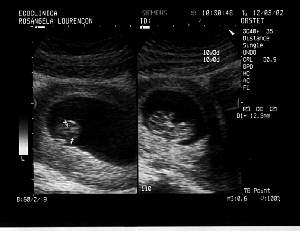

1st Session - 12th March 2002

Week: 10

Size: Around

4 cm

Obs: Mother and baby fine